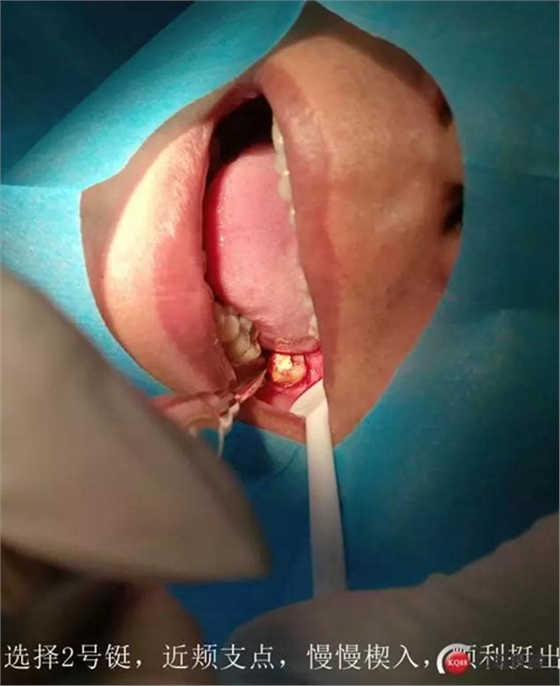

處置:38拔除

討論:對于這種炎癥感染的囊腫,囊壁基本都不完整的,可視為頜骨囊腫開窗,進行二期手術(shù),建議6個月后復(fù)查曲面。

如果強行一次完整取出,創(chuàng)傷會較大,神經(jīng)管損傷的可能性非常大,再者根尖區(qū)叩痛提示炎癥,不宜刺激

待頜骨骨壁恢復(fù)到離神經(jīng)管安全距離,再次手術(shù)比較安全。